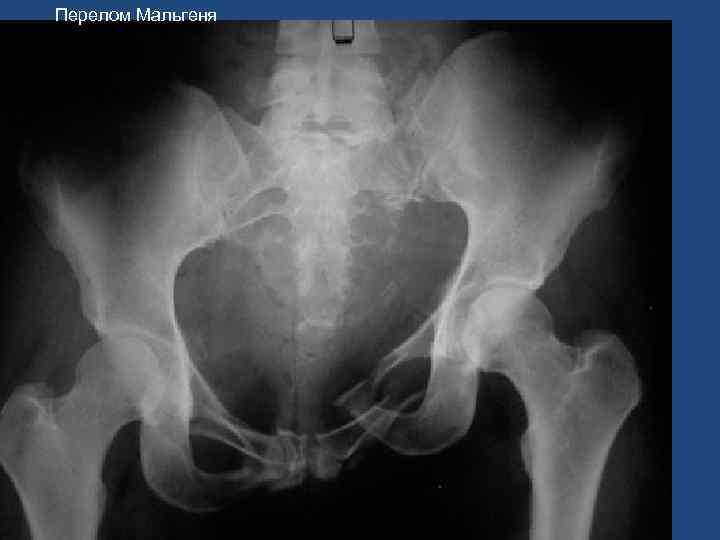

Перелом Мальгеня 46